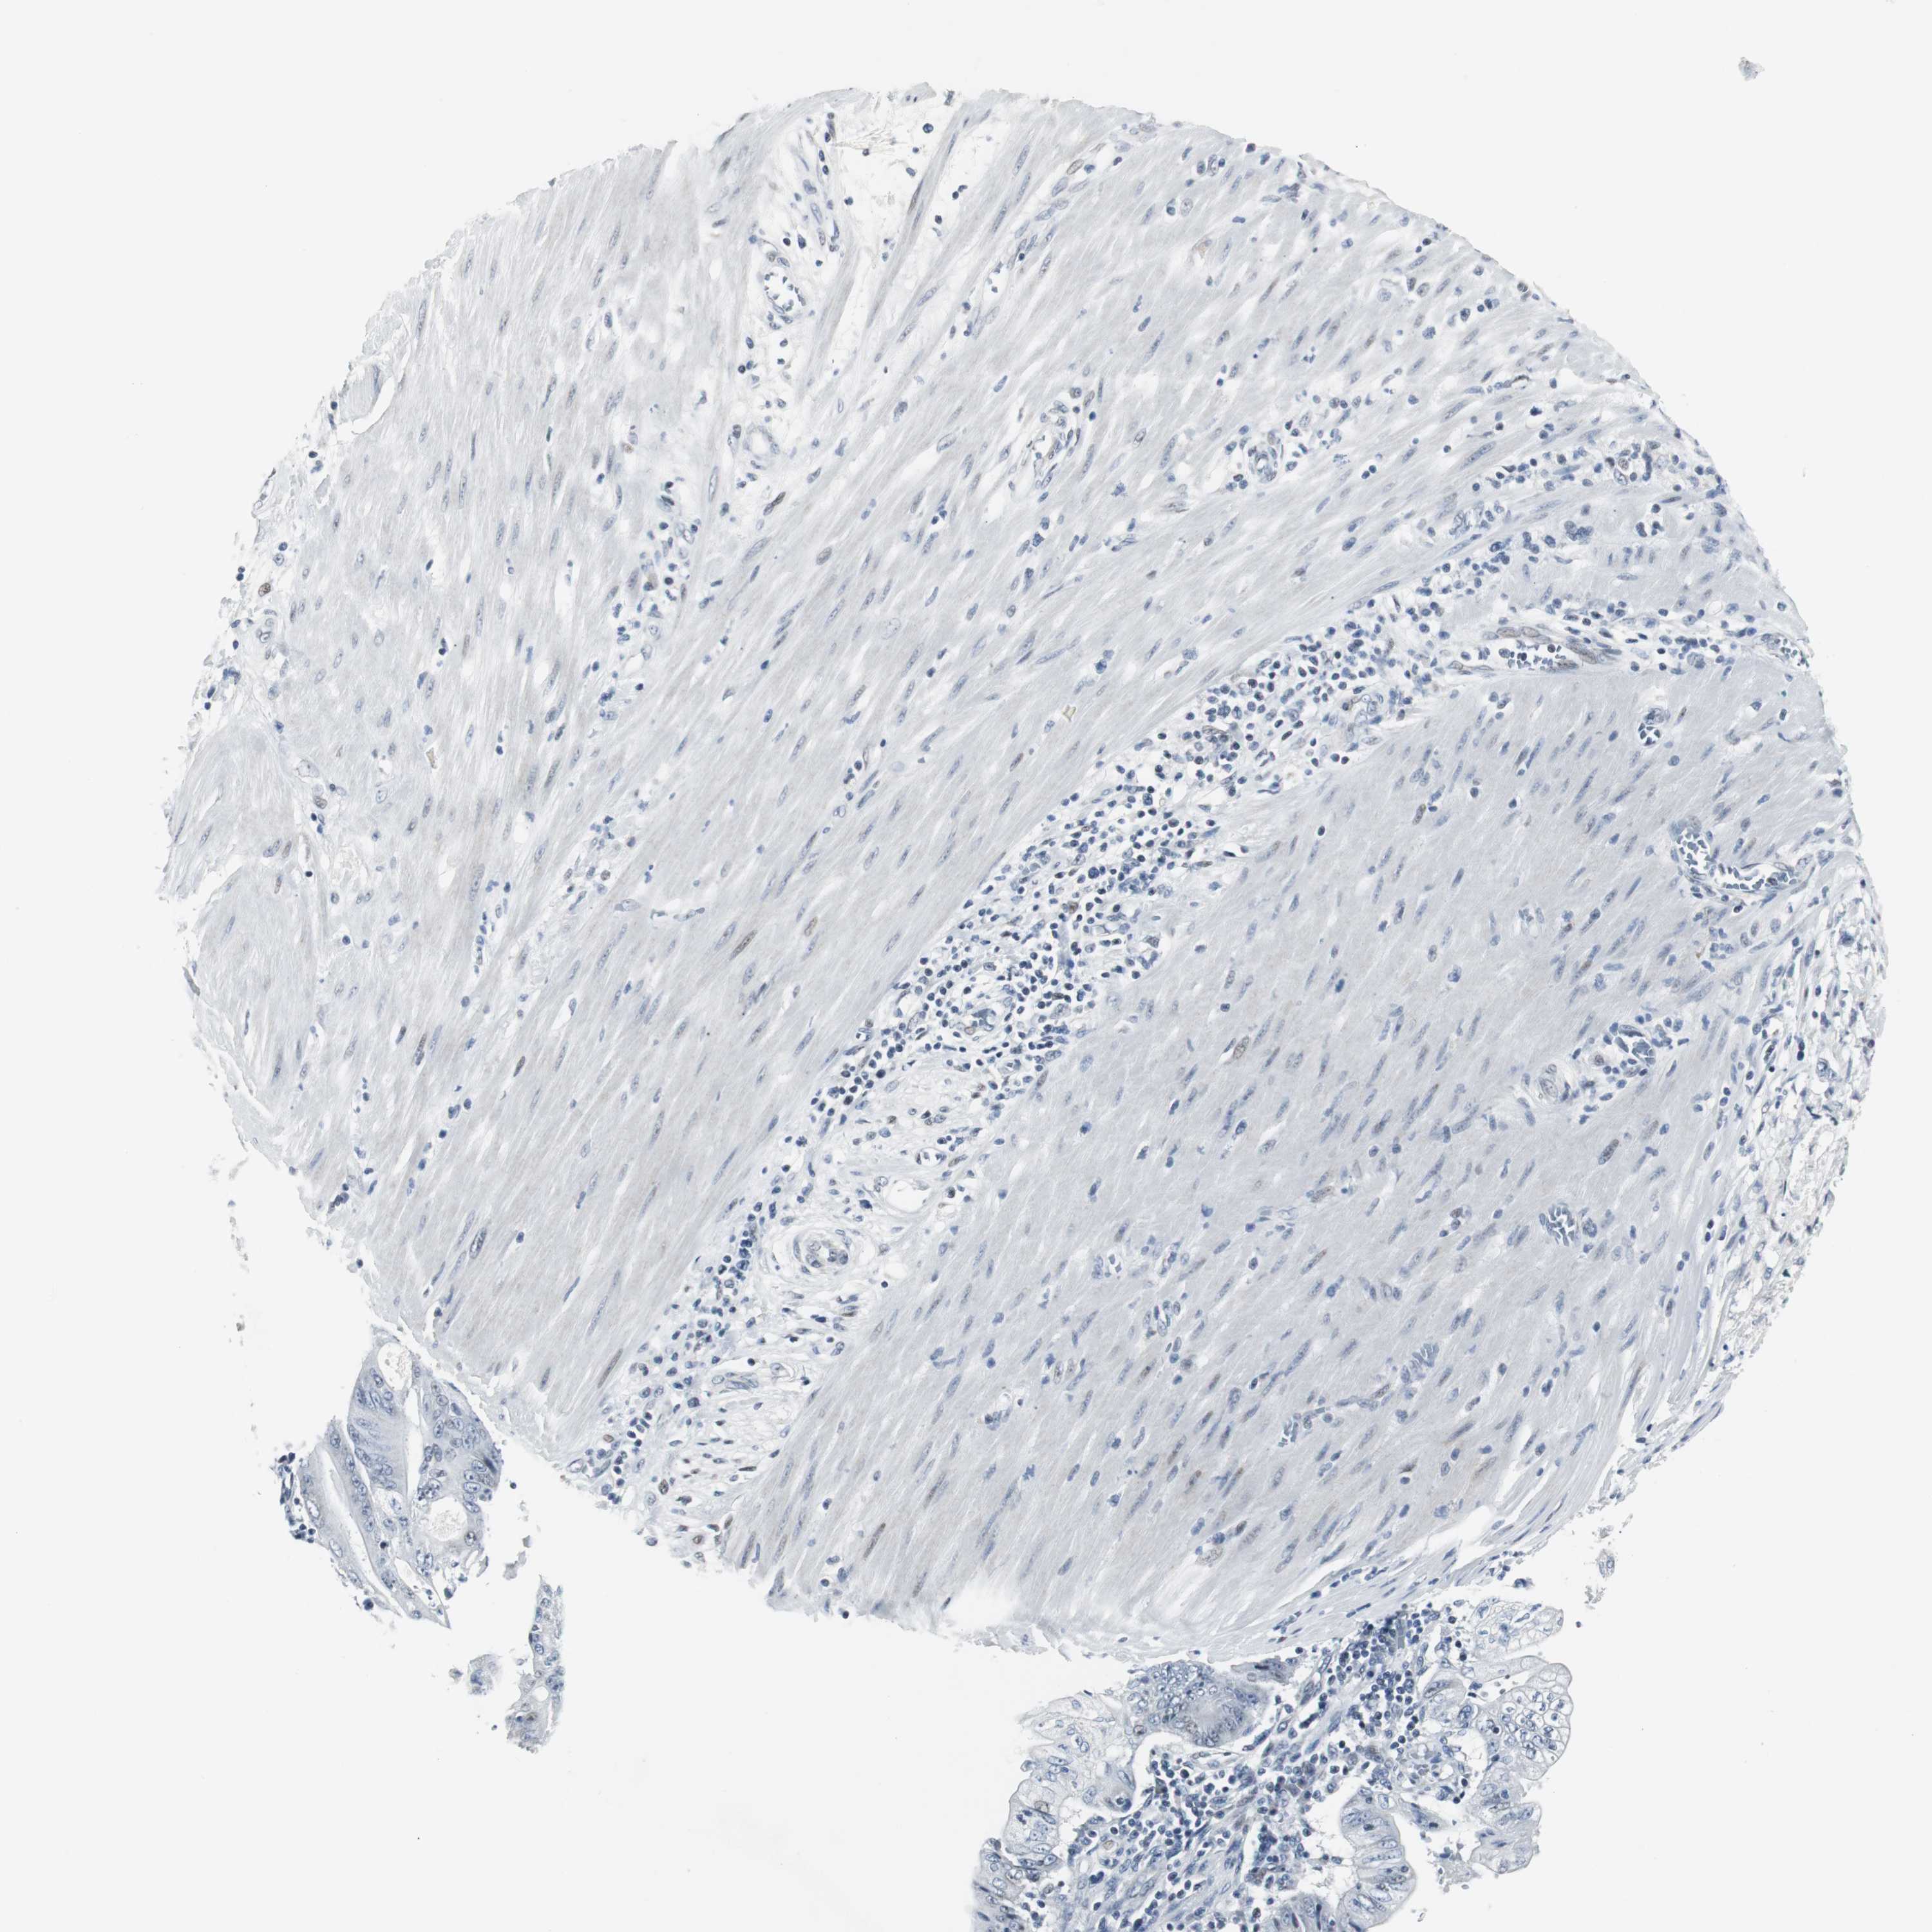

PANCREATIC CANCER - Protein expressioni

A mouse-over function shows sample information and annotation data. Click on an image to view it in a full screen mode. Samples can be filtered based on level of antibody staining by selecting one or several of the following categories: high, medium, low and not detected. The assay and annotation is described here.

Note that samples used for immunohistochemistry by the Human Protein Atlas do not correspond to samples in the TCGA dataset.

Antibody stainingi

Antibody staining in the annotated cell types in the current human tissue is reported as not detected, low, medium, or high, based on conventional immunohistochemistry profiling in selected tissues. This score is based on the combination of the staining intensity and fraction of stained cells.

Each image is clickable and will lead to virtual microscopy that enables deeper exploration of all samples and also displays staining intensity scores, fraction scores and subcellular localization as well as patient and tissue information for each sample.

Antibody HPA005544

Antibody CAB004508

Staining

High

Medium

Low

Not detected

Intensity

Strong

Moderate

Weak

Negative

Quantity

>75%

75%-25%

<25%

None

Location

Nuclear

Cytoplasmic/membranous

Cytoplasmic/membranous,nuclear